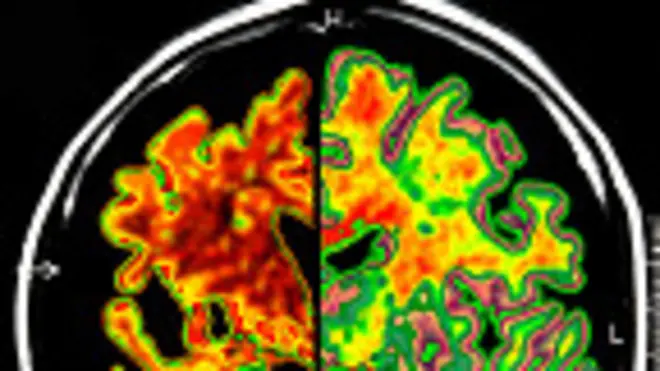

Fuente de la imagen, SPL